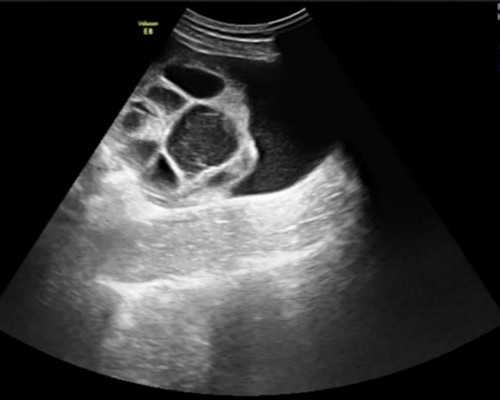

8、多胎妊娠在试管婴儿是一种高危妊娠有一个试管婴儿的例子。在做试管婴儿,第一次移植失败后,这对夫妇在试管婴儿再次成功移植,他们怀上了试管婴儿双胞胎。根据他们的身体状况,试管婴儿,医生诊断后,试管婴儿提出减胎要求,而试管婴儿夫妇则觉得自己终于怀孕了,坚决拒绝试管婴儿减胎。